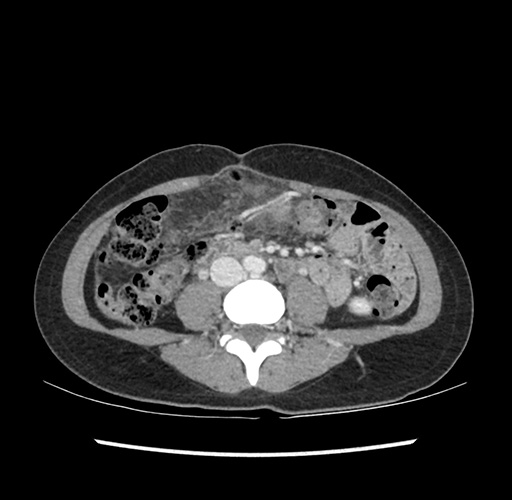

Imaging Analysis

Look through the patient's CT scan to identify any areas of concern for the necessary procedure.

Based on your CT findings, which issue(s) would give reason for "planned slowing down moment(s)" in this case?

Considering a standard left lateral sectionectomy procedure, what step(s) of the operation would you do differently in this case ?